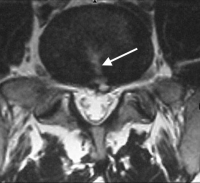

Lower back pain is very common and often the result of a minor injury or overuse. Lower back pain is one of britain's biggest health problems. Experiencing burning in the lower back is scary and can come from an assortment of different causes. .back pain suggestive of infection, low back pain suggestive of neurologic injury, low back pain suggestive of aortic aneurysm.